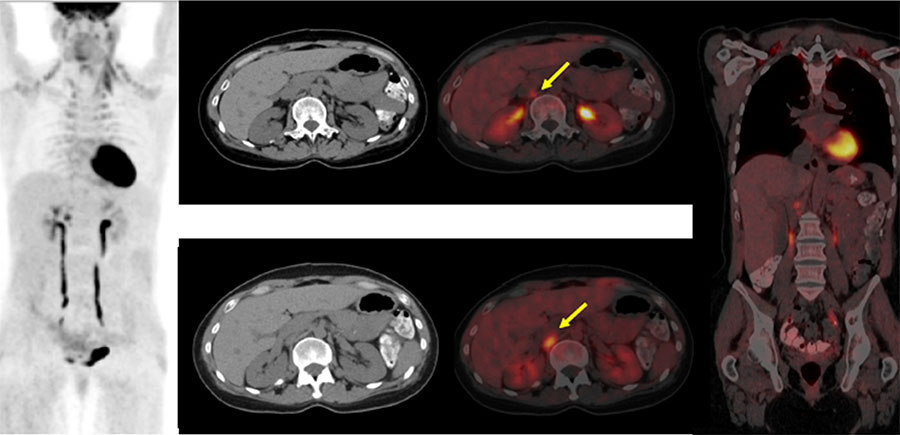

हाल आएर एक्स रे तथा रेडियोधर्मी विकिरणहरुको प्रयोग अध्याधिक र बिकशितरुपमा चिकित्सा क्षेत्रको रेडियोलोजी बिभागमा सामान्य एक्स-रे, सिटि स्क्यान, एन्जियोग्राफी आदिद्वारा, रेडियोथेरापी बिभागमा लिनियर एक्स्लेरेटर, ब्राकिथेरापी आदिद्वारा तथा न्युक्लियर मेडिसिन विभागमा गामा क्यामरा, पेट स्क्यान, स्पेक्ट स्क्यान र रेडियोन्युक्लाइड थेरापीद्वारा बिरामीको रोगहरुको परिक्षण तथा उपचारमा हुदै आएको छ ।

विकिरणको प्रयोगबाट हुन सक्ने यस्ता समस्याहरुको लेखाजोखा राख्ने तथा यससम्बन्धी जनचेतना फैलाउने कुनै निश्चित संस्थाहरु नेपालमा अझै स्थापना हुन सकेको छैन । तसर्थ नेपालमा आयनिक विकिरण तथा रेडियोधर्मि पदार्थको सुरक्षित तथा शान्तिपूर्ण प्रयोगका निम्ति ऐन तथा नियम बनाउन अत्यन्तै आवश्यक भैसकेको छ । रेडियोधर्मि पदार्थ तथा विकिरणको प्रयोग सम्बन्धी मापदण्ड तयार गर्ने नियमनकारी संस्थाको अभावमा नै हाम्रो देशमा विभिन्न प्रकारका क्यान्सरहरुको सही र सिघ्र परीक्षणका लागि चाहिने उपकरणहरु (पेट स्क्यान, स्पेक्ट स्क्यान) र रेडियोन्युक्लाइड थेरापीको पद्धतिद्वारा थाइराइड, प्रोस्टेट, निउरोइण्डोक्राइन जस्ता जटिल क्यान्सरहरुको उपचारमा प्रयोग हुने अत्यावश्यक रेडियोधर्मी पदार्थहरु जस्तै इटि्ट्रयम-९०, आयोडिन-१३१, लुटिसियम-१७७, रेहनियम-१८८, रेडियम-२२६ आदि अझै उपलब्ध हुन सकेका छैनन् ।